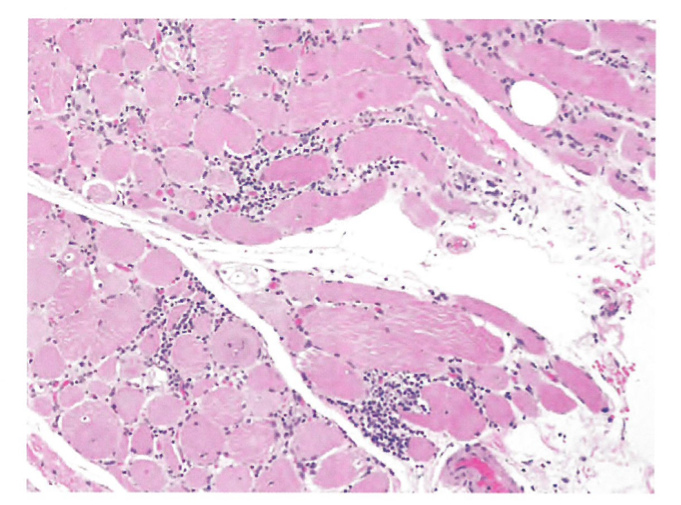

Proximal weakness and pain- diagnosis?

Polymyositis – infiltration inflammation with muscle fiber destruction (left, H&E; right, trichrome). (not rimmed vacuoles like IBM, not perifasicular inflammation like dermatomyositis)

Other histologic features include type II atrophy, fiber type grouping. Usually presents with proximal weakness and pain.

Polymyositis is an idiopathic inflammatory myopathy that typically occurs between the ages of 40 and 50.

Symptoms: Proximal weakness and pain

CK >10x normal

Treatment: Steroids +/- steroid sparing agent